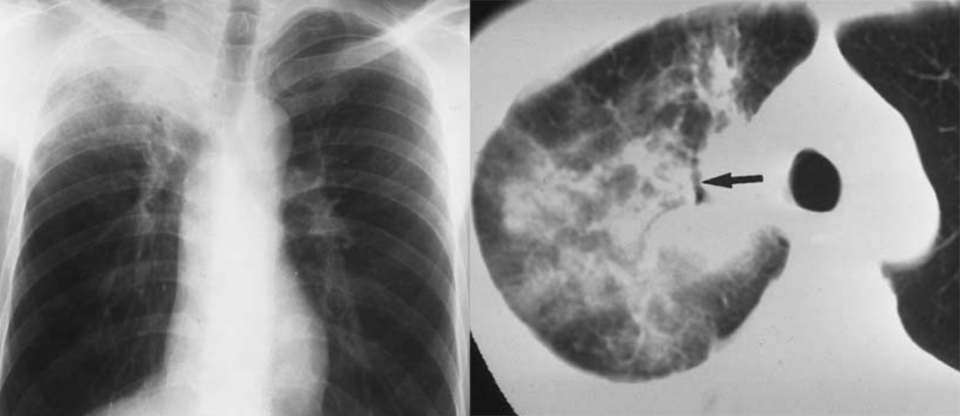

空洞性肺转移瘤

文献报道空洞型肺转移主要来自鳞癌和腺癌,鳞癌占 1/2 ~ 2/3,主要来自男性头颈部与女性生殖器肿瘤,其余为腺癌,主要来自结肠与乳腺癌。单亦有研究认为空洞性转移主要来自腺癌。其产生机制可能与鳞癌中心角化物排空、腺癌黏液样退变后黏液排空、肿瘤血供不足引起坏死、肿瘤继发脓肿、化疗、阻塞性肺气肿等有关。空洞性肺转移瘤变化快,短期内可见肿瘤增大、增多。CT 上空洞型转移结节外形上多保持了转移瘤的基本特点,即多发、圆形、边缘光整。洞壁多薄而均匀,内外壁光整,直径多 < 1.0 cm,部分洞壁厚薄不均,厚壁空洞病变可随着病灶增大而出现分叶、毛刺及壁结节等恶性空洞特点,部分空洞型肺转移洞壁可菲薄(称空泡更合适)。

乳腺癌空洞性肺转移。

54 岁男性,肾癌病史。左肺下叶厚壁空洞性转移(穿刺证实),左肺另见不伴空洞的实性小结节转移灶。

男,63 岁。食管鳞癌术后 3 年,痰中带血丝半年。穿刺证实双肺多发空洞和空泡转移,周围磨玻璃密度是转移瘤引起出血。